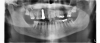

Fig 17. 12-week postoperative radiograph.

Figure 17

The final impression appointment follows the light-load phase, provided the implant is stable and the soft tissue is acceptable to the clinician. Polyvinyl putty and light-body impression materials were used in this case; analog casts and final full-zirconia full crowns were fabricated (Figure 16). The patient provided feedback that chewing was comfortable and without food impactions. Keratinized gingival cuff was developed, and natural-tooth contours for the restorations mimicked what is normally found in human dentition. The healed bone surrounding the ceramic dental implant was similar in density and crestal levels in comparison with the adjacent natural teeth, evident in the radiographic evaluation (Figure 17). Final long-term restorations at the gingival crest and restoration interfaces were also consistent in optimum periodontal health and gingival height. Arch-form integrity was upheld and occlusion was managed; osseointegration and light-load principles optimized the success of the restorations, and an acceptable, harmonious esthetic outcome was achieved for the patient.